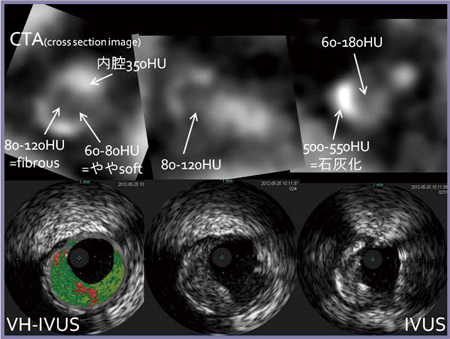

冠動脈CTAでは,プラークの性状を評価することが可能である。CT値とプラークの性状(硬さ)には相関があり,数値によってsoftプラーク(50HU以下),fibrousプラーク(50〜150HU),石灰化プラーク(500HU以上)に分けることができる。

softプラークの多い病変では,留置したステントが広がっているにもかかわらず血流が改善しない,いわゆるslow flowという合併症を起こす場合がある。これは非常に重篤な合併症であり,リスクが高い場合にはdistal protection deviceを用いる場合がある。特殊なデバイスであるため事前に準備しておく必要があり,プラークの性状についての術前の情報がきわめて重要となる。ただし,プラークのCT値はあくまで相対値であり,血管内腔の造影剤充填につれて変化することに注意が必要である。

症例2では,半月形のfibrousプラークと末梢の表面の石灰化,そして,近位部のfibrousプラークの一部に軟らかいスポットが確認された。血管内エコー(IVUS)でも,同様の所見が得られている(図5)。

図5 症例2:CT値によるプラークの性状評価(上段)とIVUS画像(下段)